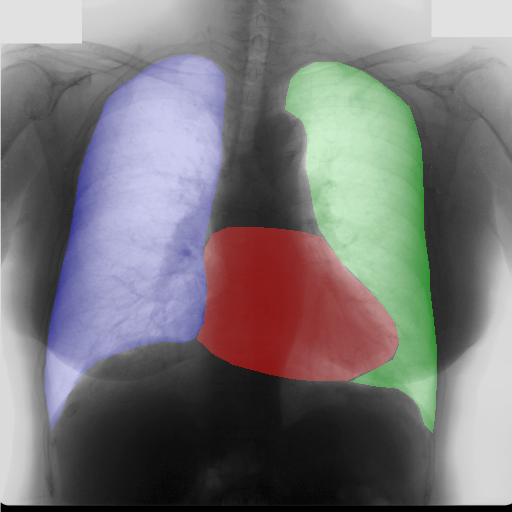

Moreover, in order to clarify the limits of the three–stage method, we assessed the quality of the segmentation results based on three human experts, who were asked to check 20 chest X–ray images, along with the corresponding supervision and the segmentation obtained by the SMANET network. Such images were chosen among those that can be considered difficult, at least based on the high error obtained by the segmentation algorithm. Figure 7 and Figure 8 show different examples of the images evaluated by the experts. The first column represents the chest X–ray image, while the second and the third columns, whose order was randomly exchanged during the presentation to the experts, represent the target segmentation and our prediction, respectively. The three physicians were asked to choose the best segmentation and to comment about their choice. Apart from a general agreement of all the doctors on the good quality of both the target segmentation and the segmentation provided by the three–stage method, surprisingly, they often chose the second one. For the examples in Figure 7, for instance, all the experts share the same opinion, preferring the segmentation obtained by the SMANET over the ground–truth segmentation. To report the results of the qualitative analysis, we numbered the target and predicted segmentation with 1 and 2, respectively, while doctors were assigned unordered pairs to obtain an unbiased result. Then, with respect to Figure 7(a), the comments reported by the experts were: 1) In segmentation 1, a fairly large part of the upper left ventricle is missing; 2) I choose the segmentation number 2 because the heart profile does not protrude to the left of the spine profile; 3) The best is No. 2, the other leaves out a piece of the left free edge of the heart, in the cranial area. Instead, for Figure 7(b), we obtained: 1) The second image is the best for the cardiac profile. For lung profiles, the second image is always better. The only flaw is that it leaks a bit on the right and left costophrenic sinuses. 2) Image 2 is the best, because the lower cardiac margin is lying down and does not protrude from the diaphragmatic dome. Image number 1 has a too flattened profile of the superior cardiac margin. 3) No. 2 for the cardiac profile more faithful to the real contours.

Instead, they reported conflicting opinions or decided not to give a preference with respect to the examples in Figure 8. When they agreed, they generally found different reasons for choosing one segmentation over the other. With respect to Figure 8(a) the comments reported by the experts were: 1) I prefer not to indicate any options because the heart image is completely subverted; 2) Segmentation number 2 is better, even if it is complicated to read because there is a “bottle–shaped” heart. The only thing that can be improved in image 2 is that a small portion of the right side of the heart is lost; 3) No. 1 respects more what could be the real contours of the heart image. Instead, for Figure 8(b) we obtained: 1) I prefer No. 2 because the tip of the heart is well placed on the diaphragm and does not let us see that small wedge–shaped image that incorrectly insinuates itself between heart and diaphragm in image 1 and which has no correspondence in the RX; 2) Both are good segmentations. Both have small problems, for example: in segmentation 1 a small portion of the tip (bottom right of the image) of the heart is missing, in segmentation 2 a part of the outflow cone (the “upper” part of the heart) is missing. It is difficult to choose, probably better No. 1 because of the heart; 3) No. 2 because No. 1 carnally probably exceeds the real dimensions of the cardiac image, including part of the other mediastinal structures.

These different evaluations, albeit limited by the small number of examined images, confirm the difficulty of segmenting CXRs, a difficulty that is likely to be more evident in the case of the images selected for our quality analysis, which were chosen based on the large error produced by the segmentation algorithm.